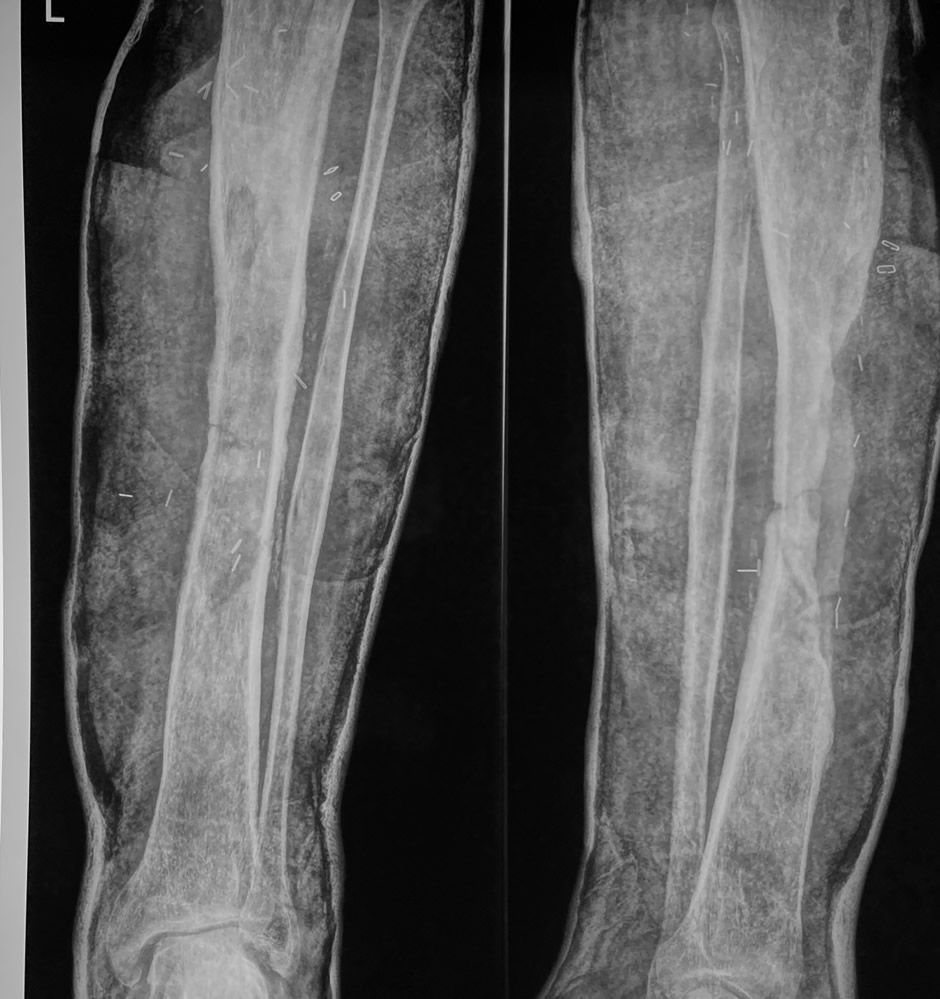

Diagnóstico: Osteomielitis crónica masiva de tibia

Paciente de 71 años que acude por osteomielitis de tibia de 30 años de evolución. Nunca se aplicó tratamiento adecuado. Sólo se le propuso amputación de la extremidad.

El paciente llevaba 30 años con una osteomielitis crónica masiva de tibia sin haber recibido tratamiento adecuado en ningún momento. La única alternativa que se le había ofrecido era la amputación. La edad avanzada y la extensión de la afectación ósea convertían este caso en un reto reconstructivo de alta complejidad.

Paso 1: Resección radical de todo el hueso avascular y/o infectado y cobertura con colgajo microvascular latissimus dorsi

Se eliminó la totalidad del hueso avascular e infectado dejando sólo 1/3 de la circunferencia de la tibia. El defecto se rellenó con un colgajo microvascular latissimus dorsi.